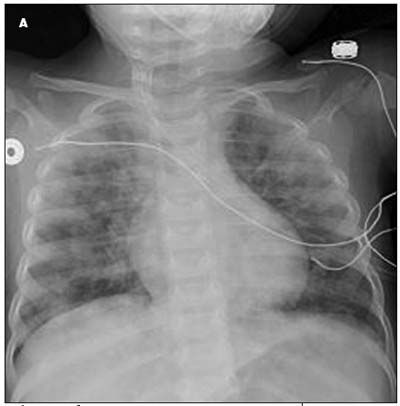

Chest examination revealed a quiet precordium with normal breath sounds bilaterally. A chest radiograph showed bilateral pulmonary infiltrates (A). An arterial line was placed. Blood gas analysis showed a pH of 7.45; PCO2, 29 mm Hg; and PO2, 116 mm Hg. With the possible diagnosis of pulmonary hemosiderosis (PH), intravenous corticosteroid therapy was initiated.